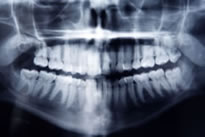

歯の状態・形などを把握し、目視では確認できない症状がないか調べるため、別室にご案内してレントゲン撮影をいたします。レントゲン撮影で患者様のお口の中を正確に把握することにより、より良い治療につなげることが可能となります。